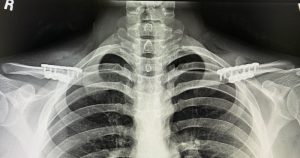

The placement of the incision is directly above the best location to remove the segment of clavicle bone which is at its inner third. This is the thickest part of the clavicle by cross-sectional diameter and is also the most stable being closest to the sternum. The small skin incision is placed, not over the bone, but up above in the supraclavicular fossa which provides for the most favorable scar healing. The segment of bone removed is typically in the range of 2.0 to 3cms per side. Short rigid plate and screw fixation of the shortened clavicle is used for stabilizing the two bone ends. This results in a bideltoid width reduction of 5 to 6 cms which creates a a more narrow and slightly rounded shoulder appearance. This has also been shown to result in uncomplicated bone healing and no adverse effects on shoulder function.

One year postop

Combining breast augmentation (425cc silicone implants) with shoulder narrowing surgery.